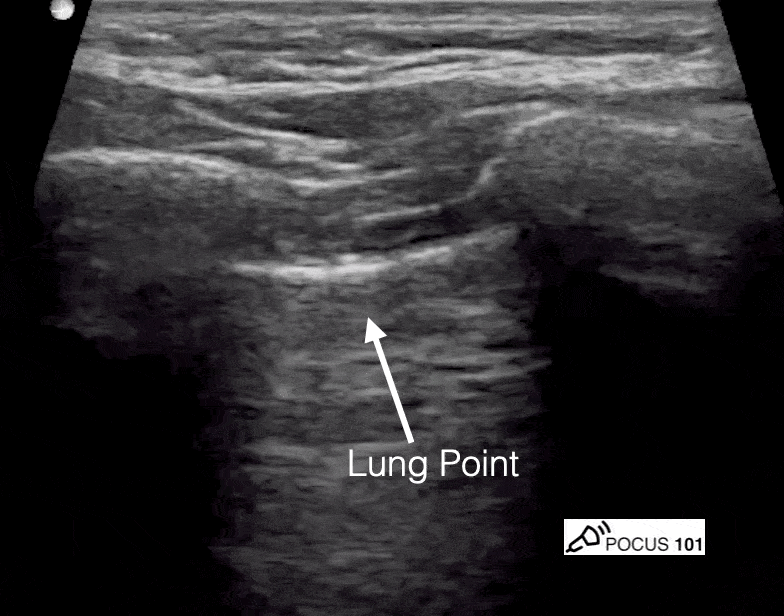

Lung point, however, is far more specific for PTX but this was not found in this case. (thanks @pocus101)